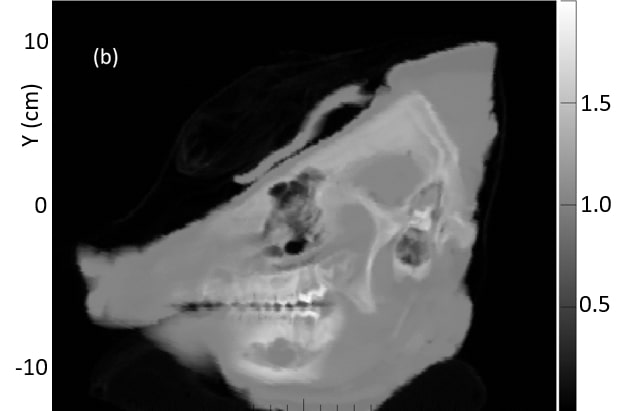

Fig. 8 shows a comparison of the average of ten 1 mm sagittal slices from a lateral region of the pig’s head for pCT and the vertical x-ray CT, in order to reduce noise. Features are slightly blurred due to their change in shape with depth. The grey scale reflects the measured RSP, whereas in Fig. 6 and 7 the grey scales were windowed and levelled to optimize contouring. The largest differences are in regions of heterogeneity such as the teeth and tympanic bullae.

The difference map also clearly shows the systematic discrepancy in the skull and the mandible, while soft tissue regions such as brain and muscle regions show closer agreement. The difference in the tip of the snout is caused by an incomplete set of pCT data through that area. The pencil beam scans used for the pCT data set only covered a cm2 area, so the tip of the snout was not quite covered at lateral angles.